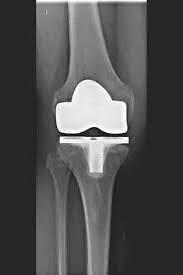

يحل مفصل الركبة الاصطناعي محل سطح الغضروف الذي دمره التهاب المفاصل العظمي. يظل العظم الأساسي في عظم الفخذ والرأس الظنبوبي سليمًا. يقارن البعض مفصل الركبة الاصطناعي الحديث بتتويج الأسنان؛ والمصطلح الدقيق هو ما يسمى بإعادة تسطيح اللقمتين. بين الأسطح الجديدة في الجزء العلوي والسفلي من الساق يوجد ما يسمى بالبطانة المصنوعة من البلاستيك الأبيض المقوى خصيصًا، والتي يمكن رؤيتها في صورة الأشعة السينية على أنها المسافة بين الأجزاء المعدنية.